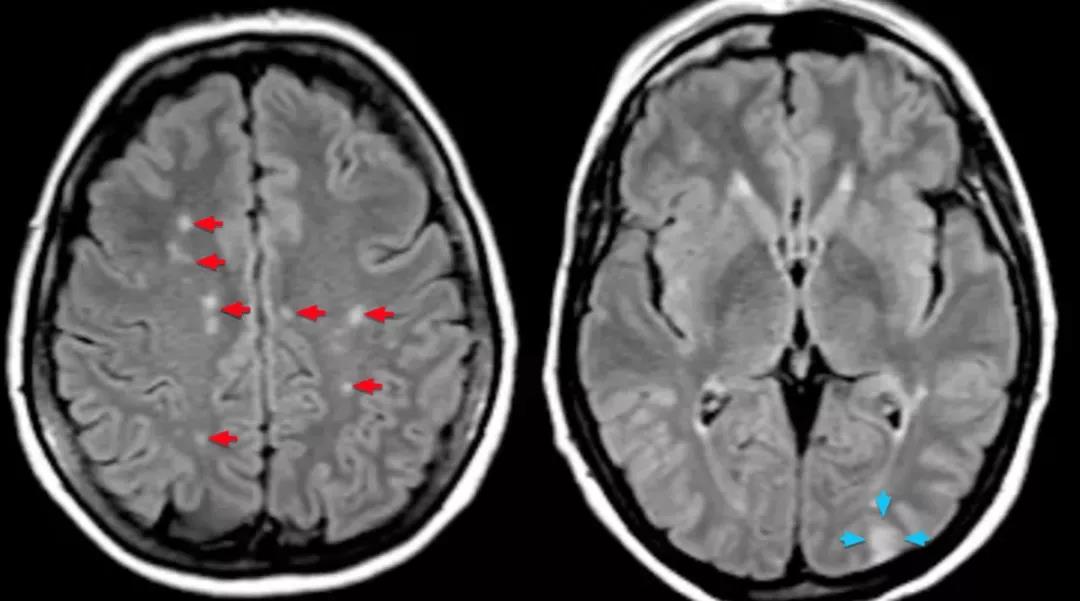

病变部位比脑血管病的性质更重要,侵犯大脑皮质的病变不论出血或缺血均比大脑深部的病变发生癫痫的可能性大,皮层病变癫痫的发生率可达40%左右,如脑叶出血或分水岭梗塞;深部病变仅为3%左右。

脑叶出血是指出血在额、顶、枕或颞叶中的某一叶,出血部位较浅表,皮质常受侵犯,皮质受侵犯就直接影响神经细胞的功能,包括电位的异常,因而易于出现#癫痫#发作。

分水岭梗塞指的是在大脑两个动脉分布区的接壤处发生梗塞,这个部位的的特点就像地理上的分水岭,是供血最薄弱的区域,也在大脑浅表区,缺血后明显影响皮质神经元的功能。